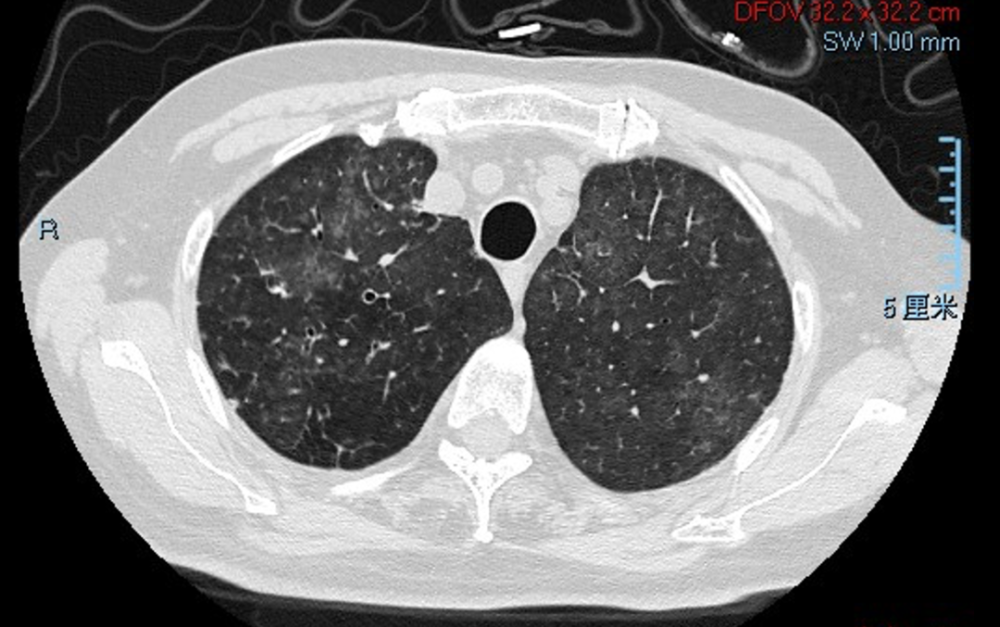

胸部CT(2021-1-13)